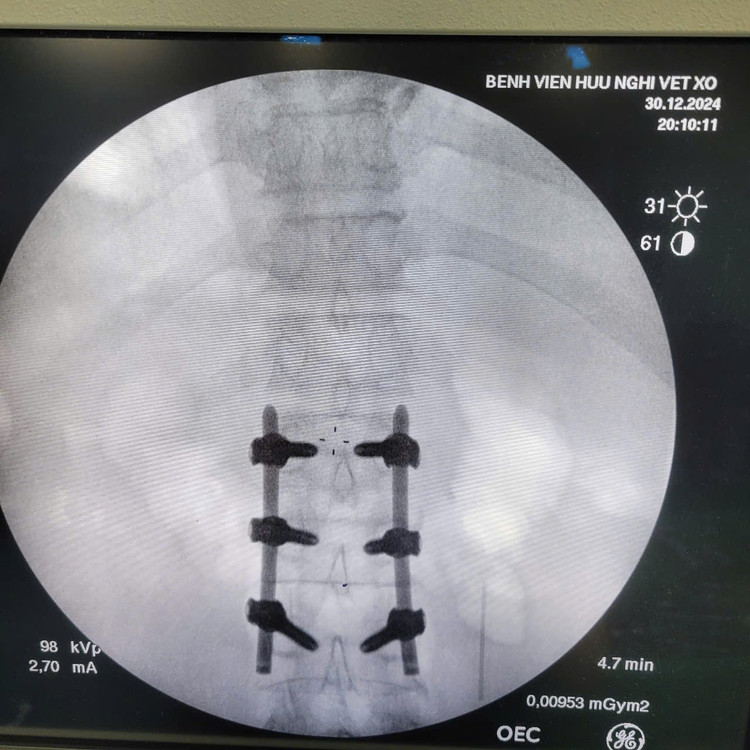

Ca phẫu thuật cho bệnh nhân - Ảnh BVCC

Cột sống được cố định vững - Ảnh BVCC

Sử dụng hệ thống máy C-arm, dẫn đường hình ảnh (navigation) để đặt vít chính xác tuyệt đối, tránh tổn thương tủy sống và rễ thần kinh.